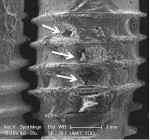

+ Minimal treatment effect = some cement removal from crest of implant threads, no cement removal from the concavities between threads (Figure 2 and Figure 3).

++ Moderate treatment effect = removal of cement from crest of implant threads, some cement removal between threads, but minimal exposure of the subjacent implant surface (Figure 4 and Figure 5).

+++ Mostly effective treatment = removal of cement from crest of implant threads and most of the cement between threads, with exposure of most of the subjacent implant surface (Figure 6 and Figure 7).

The CO2 9300 nm laser visibly removed most of the cement on all three implant surfaces and showed minimal surface changes under SEM (Figure 6 and Figure 7), while the Er,Cr:YSGG and Er:YAG lasers and the Nd:YAG laser alone had a minimal effect on the cement and implant surface (Figure 2 and Figure 3). Cement removal by the CO2 10,600 nm laser as a monotherapy was variable depending on the surface tested.

Table 1 reveals that none of the treatment modalities was completely successful at removing all cement from the implant test surfaces. Post-treatment SEM evaluation was carried out to obtain magnified views of residual cement and assess damage to the implant surface that might have occurred as a result of treatment. The effectiveness of cement removal varied markedly, with the implants treated with the CO2 9,300 nm laser protocol being mostly free of cement (Figure 6 and Figure 7) and the Er,Cr:YSGG and Er:YAG lasers (Figure 2 and Figure 3) and Nd:YAG laser (as a monotherapy) being minimally effective. When used as part of a dual therapy in conjunction with the piezo scaler, the Nd:YAG, CO2 10,600 nm, and diode lasers were only marginally more effective than the piezo scaler alone.